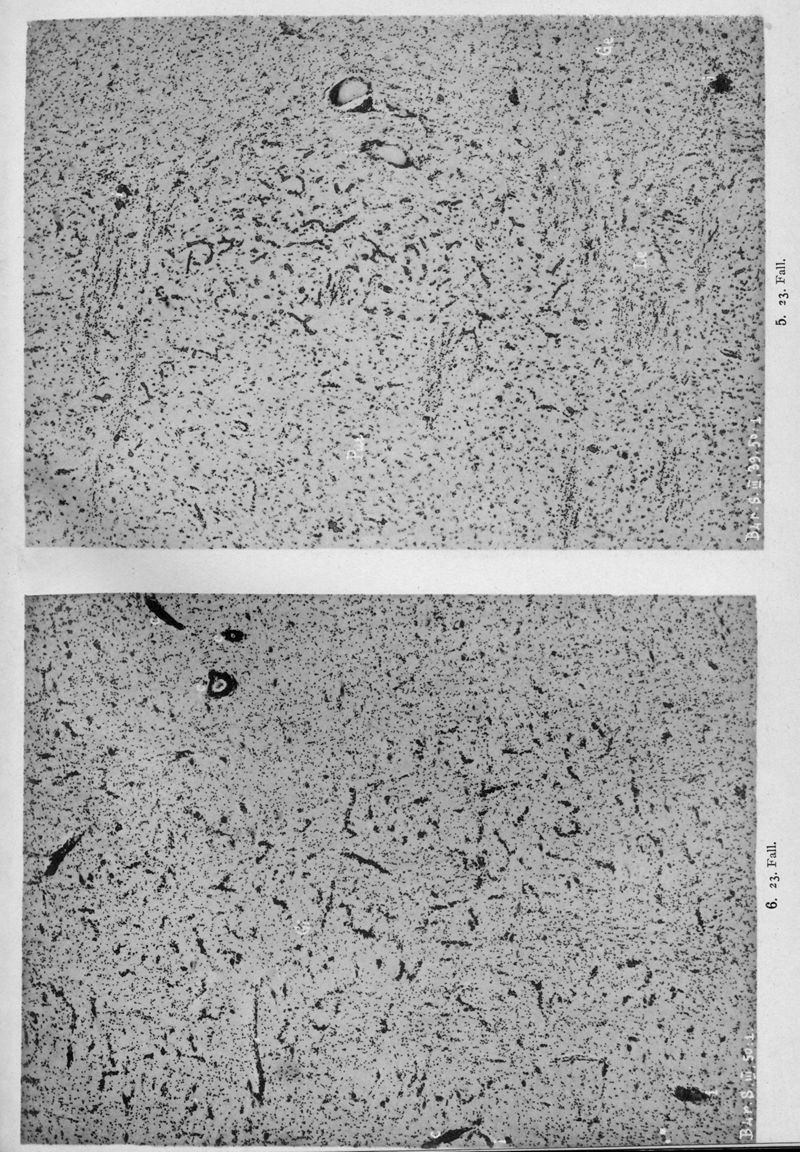

VOGT, Cécile / VOGT, O.

In : Journal für Psychologie und Neurologie,

1920, Vol. 25, pp. 627-846